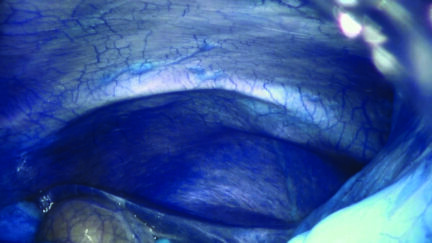

The final part of Ancarani’s trilogy is set in an operating theatre where a fabulous journey through the human body is undertaken by robot arms, with the surgeon at the joystick. Science fiction-like, it is reminiscent of Fantastic Voyage (1966). Ancarani captures the whole operation with minute precision, beautifully lit (no bloody effects) like a dazzling choreography accompanied by an exciting soundtrack.